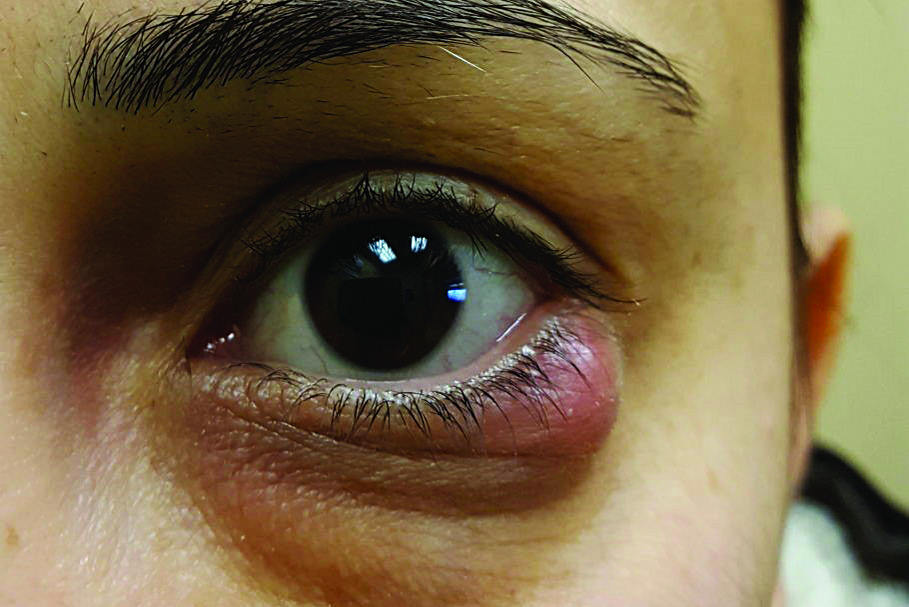

The patient in question, a male in his mid 20s, presented to our practice after living in another part of the country for several years. He has an interesting case of monocular keratoconus in his left eye and has worn a KATT scleral lens from Capricornia in the past. However he lost this lens a year prior and has been getting by with using a spherical monthly silicone hydrogel lens to correct the low myopia in his normal right eye.

Refraction was R -2.00/-0.25 x 90 (6/5), L -1.25/-6.50 x 132 (6/20+). Corneal topography revealed an essentially normal pattern in the right eye and a steep central area with surprisingly regular astigmatism in the left eye. Keratoconus was confirmed with pachymetry showing relative thinning in the left eye: R 562µm, L 530µm. Slit-lamp examination revealed no corneal opacity in either eye.